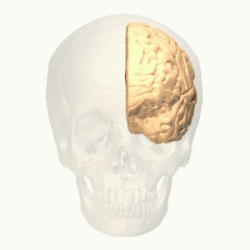

![]() Medial surface of left cerebral hemisphere, with anterior cingulate highlighted | |

In human brains, the anterior cingulate cortex (ACC) is the frontal part of the cingulate cortex that resembles a "collar" surrounding the frontal part of the corpus callosum. It consists of Brodmann areas 24, 32, and 33.